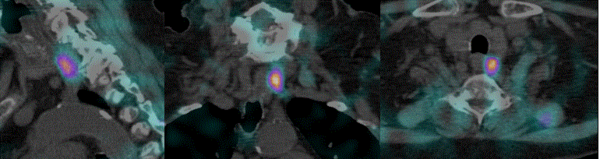

L’une des causes fréquentes d’hyperparathyroïdie est l’adénome parathyroïdien. La mise en évidence de cet adénome n’est pas toujours aisée et l’apport de la technique SPECT/CT est un bon atout diagnostique (2).

En effet, le SPECT/CT  apporte une valeur additionnelle en permettant  de guider le geste chirurgical. Le SPECT/CT permet d’identifier simultanément la zone métaboliquement pathologique et la localisation anatomique précise (profondeur du foyer et position par rapport aux structures environnantes et adjacentes). Ceci est illustré par la figure 6 qui met clairement en évidence un adénome parathyroïdien gauche.

Le SPECT/CT peut également être réalisé après une première chirurgie n’ayant pas abouti à l’exérèse d’un adénome, notamment pour rechercher une localisation ectopique.

Figure 6